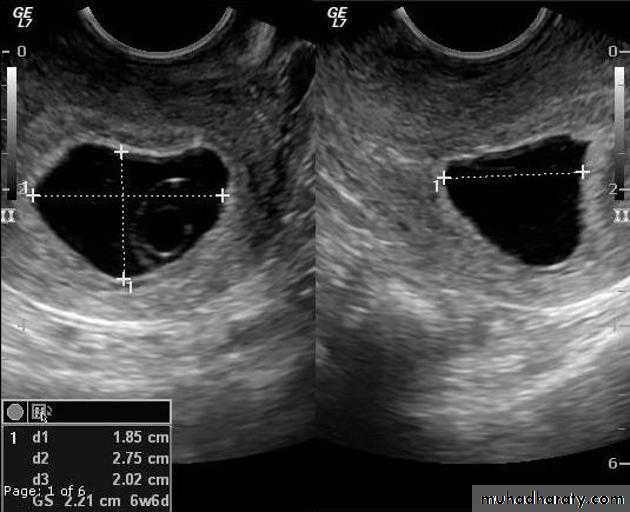

Blighted ovum

Anembryonic pregnancy is a form of a failed early pregnancy, where a gestational sac develops, but the embryo does not form. The term blighted ovum is synonymous with this, but is falling out of favour and is best avoided.Radiographic features

Ultrasound

An anembryonic pregnancy may be diagnosed when there is no fetal pole identified on endovaginal scanning , and:

the size of the gestational sac is such that a fetal pole should be seen: MSD ≥25 mm on TVS (by RCOG criteria)